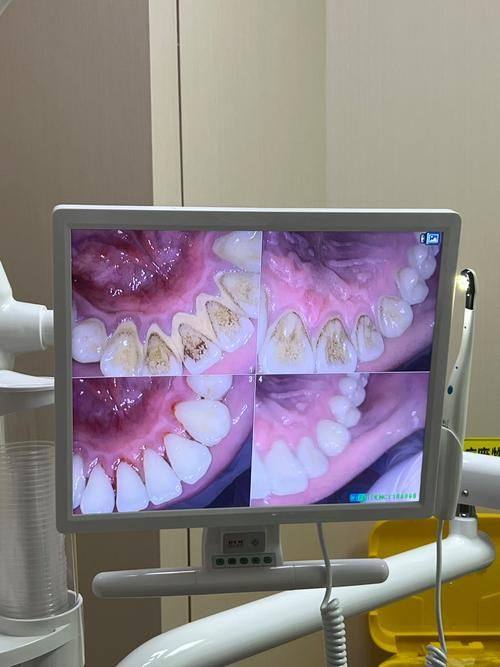

特别多人担心洗牙会伤害牙齿,其实正常情况下,正确的洗牙对牙齿是没有损害的。我们牙齿表面的牙釉质硬度非常高,洗牙过程中产生的影响几乎可以忽略不计。而且洗牙时用来抛光的橡皮轮材质特别软,不会对牙齿造成磨损。洗牙的主要作用是洗掉那些长时间刷牙都没刷干净的牙菌斑和牙结石。这些脏东西如果一直留在牙齿上,会对牙齿健康造成较大威胁。所以,从这个角度看,洗牙不仅不会伤害牙齿,反而对牙齿健康有益。

洗牙能去除牙菌斑和牙结石,这可是预防龋坏和牙周病的有效办法。牙菌斑和牙结石是导致龋齿和牙周病的主要原因。如果不及时清除,细菌会在牙齿表面滋生,破坏牙齿的结构,引发疼痛和炎症。通过洗牙,把这些“隐患”清除掉,就能大大减少龋坏和牙周病的发生几率。所以,洗牙其实是一种保护牙齿的重要手段。

虽然洗牙对牙齿有好处,但经常洗牙可就不好了。如果洗牙过于频繁,会损伤牙齿表面,可能会形成划痕或隐裂,还会损害牙冠表面的牙釉质。牙釉质一旦受损,牙齿就会变得敏感,容易受到外界刺激。一般来说,建议半年到一年洗牙一次。这样的频率既能清除牙颈部的食物残渣、软垢和新生的牙石,又能保护牙周组织的健康。